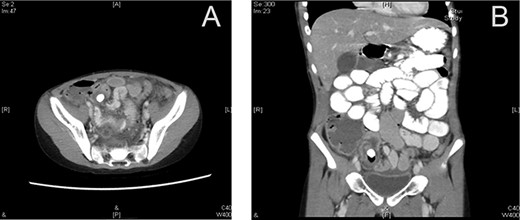

Laboratory investigations showed following results: white blood cell count 24.00 × 103/μl (reference range 4.5–11), hemoglobin 13.6 g/dl (reference range 13–16), C-reactive protein 76.5 (<5 nl). A computed tomography (CT) scan of the abdomen and pelvis using oral and intravenous contrast showed a distended appendix filled with fluids (Fig. 1). Also observed were pockets of air with a larger proximal and smaller distal fecolith with free fluid in Morison’s pouch, right paracolic gutter and rectovesical pouch consistent with acute complicated appendicitis.

Preoperative CT scan (axial section) showing a dilated appendix with an enhanced wall filled with fluids and air pockets (A). A large appendicolith was noted. The coronal section shows a dilated appendix with an enhanced wall filled with fluids and air pockets. A large appendicolith was noted (B).